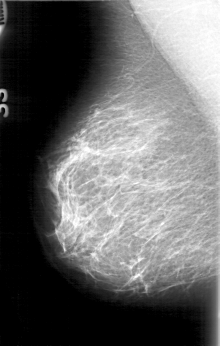

D_4075_1.RIGHT_MLO

RIGHT_CC LINES 5266 PIXELS_PER_LINE 3076 BITS_PER_PIXEL 12 RESOLUTION 43.5 NON_OVERLAY

RIGHT_MLO LINES 5176 PIXELS_PER_LINE 3286 BITS_PER_PIXEL 12 RESOLUTION 43.5 NON_OVERLAY